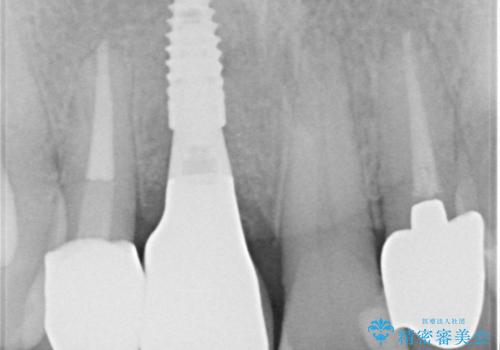

レントゲン写真では判断することは困難でしたが、右上の中切歯は歯根破折が疑われ、右上の側切歯は根尖部の病変に由来する痛みが認められました。

側切歯は根管治療を行い、中切歯部は骨の再生を待ってインプラントを埋入し、その後2本合わせてオールセラミッククラウンにて補綴治療を行うこととしました。